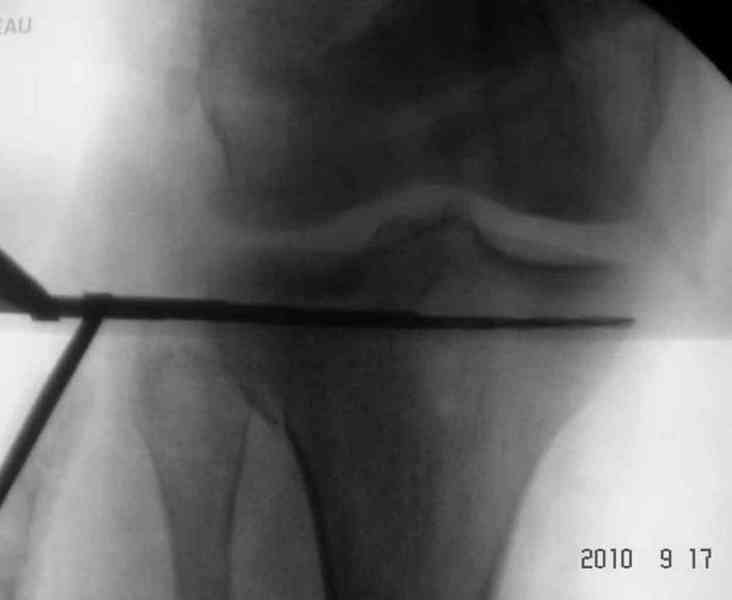

Вчера выполнена закрытая репозиця малоберцовой кости, промежуточный отломок расклинен с дистальным метаепифизом, выведен ближе к оси центрального отломка, вилка голеностопного сустава стала нормальной конфигурации, уменьшен вес вытяжения. Снимки представлю завтра.

На будущей неделе планируем открытую репозицию внешнего мыщелка левой б/б кости с костной пластикой и фиксацией пластиной. Открытая репозиция малоберцовой, синтез 1/3 пластиной, открытая репозиция сустаной поверхности, синтез, и тут проблема - в имеющихся в наличии пластинах нет необходимой длины для фиксации-мост к центарльному отломку. Как поступить? АВФ?

Снимки до и после закрытой репозиции

Пациентки прооперирована, результат чего на снимках. Выполнена открытая репозиция костей правой голени, синтез малоберцевой пластиной, б/берцевой винтами, имеющиеся фиксаторы не подходили, было принято решение репонировать отломки, синтез винтами, гипсовая повязка.

Мыщелок левой б/б кости репонирован закрыто, на контрольной рентгенограмме репозиция удовлетворительная, фиксировано спицами. гипсовая повязка.